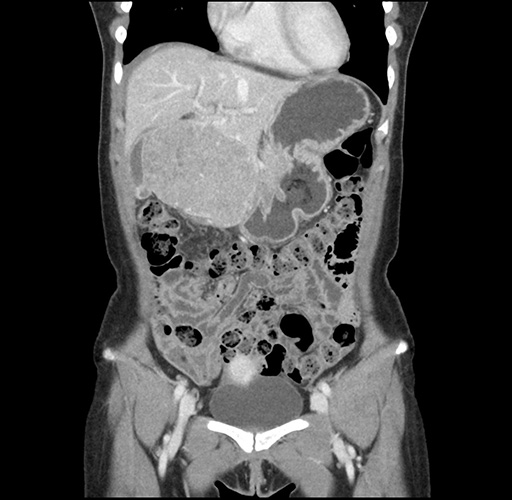

Left lateral sectionectomy [case 12]

Imaging Analysis

Look through the patient's CT scan to identify any areas of concern for the necessary procedure.

Based on your CT findings, which issue(s) would give reason for "planned slowing down moment(s)" in this case?

Considering a standard left lateral sectionectomy procedure, what step(s) of the operation would you do differently in this case ?